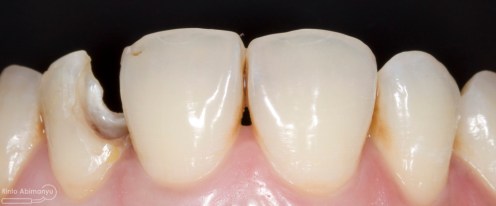

Kasus hari ini ceritanya datang seorang pasien wanita usia sekitar 50 an mengeluhkan gigi2 atas kirinya sering terselip makanan dan terkadang terasa senut-senut…

Pada pemeriksaan intra oral terlihat gigi 23 dan 24 mengalami karies dan cukup banyak sisa makanan terjebak disana…